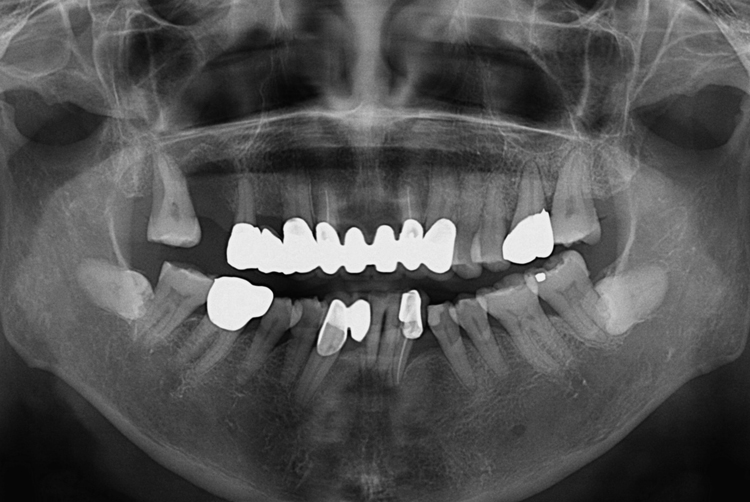

치료사례

세종치과의 진심 어린 치료는 결과로 말합니다.

실제 내원하신 환자분들의 치료 전·후 사례를 확인해보세요.

모든 치료사례 전후사진은 환자분의 동의하에 촬영되었습니다.

모든사진은 동일 환자분의 전후모습을 촬영하였으며, 사진의 밝기조절 외에 임의 수정이 없음을 알려드립니다.